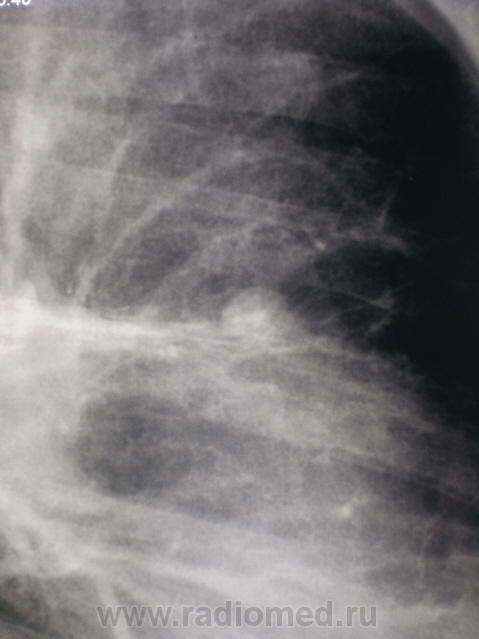

метастазы в легкие и плевру

был задан об одной "круглой тени" в S3. Решил, что гамартохондрома. Присмотревшись к окружающему фону и плевральным изменениям слева, не исключаю туберкулёму.

А та, что красной стрелкой помечена, по всей видимости, более молодая её сестра?

действительно круглая тень имеет плотный кальцинированный центр,что практически не характерно для злокачественных изменений за исключением метастазов из первичых опухолей кости (они в 90% случаев имеют кальцинаты на периферии ,а не в центре!!!).а так 3 диагноза:1)туберкулема,2)гамартома,3)гистоплазмоз.на счет участков выше ,если присмотреться повнимательнее ,то участок представляет собой сгруппировавшиеся мелкие (ацинарные) очаги по типу дерева в почках,отражающий эндобронхиальный рост,выпот слева-так что в первую очередь надо исключить туберкулез

Я, конечно, сильно извиняюсь, но кажется и правом лёгком не меньше округлых теней. Да и реакция плевры, полюс левосторонний гидроторакс. Искать, искать и ещё раз искать (всегда думал В.И.Ленин)

Ну так там еще есть в ср/доле...